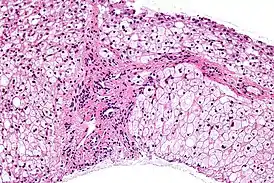

![]() Микрофотография: накопление гликогена в клетках печени (окраска гематоксилином и эозином). | |

Болезнь сопровождается отложением атипичного гликогена в печени, сердце, мышцах.